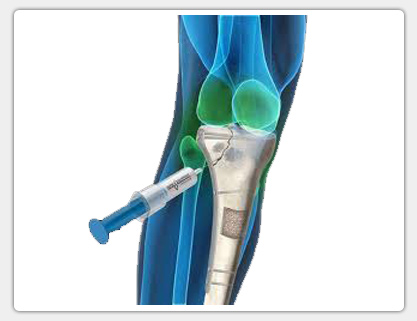

Synthetic Bone Substitute